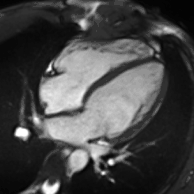

Atrial septal defect with dilation of the right ventricle by CMR

Partial Anomalous Pulmonary Venous Drainage by CMR

Enlarged right ventricle with poor function in a patient with repaired tetralogy of Fallot by CMR